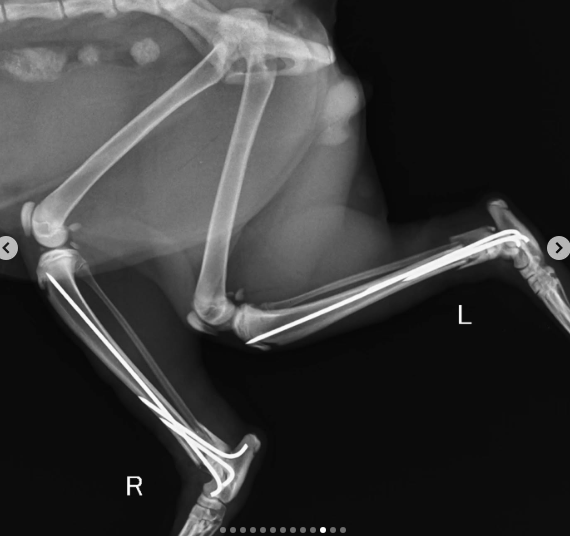

After going from pillar to post and getting no help, his feeder reached out to me. She had first aid done and was wondering what to do next as Timon needed urgent and intensive intervention. His bones were crushed and one was jutting out.

We got various opinions and decided to admit Timon at @petology_clinic where Timon underwent surgery yesterday.